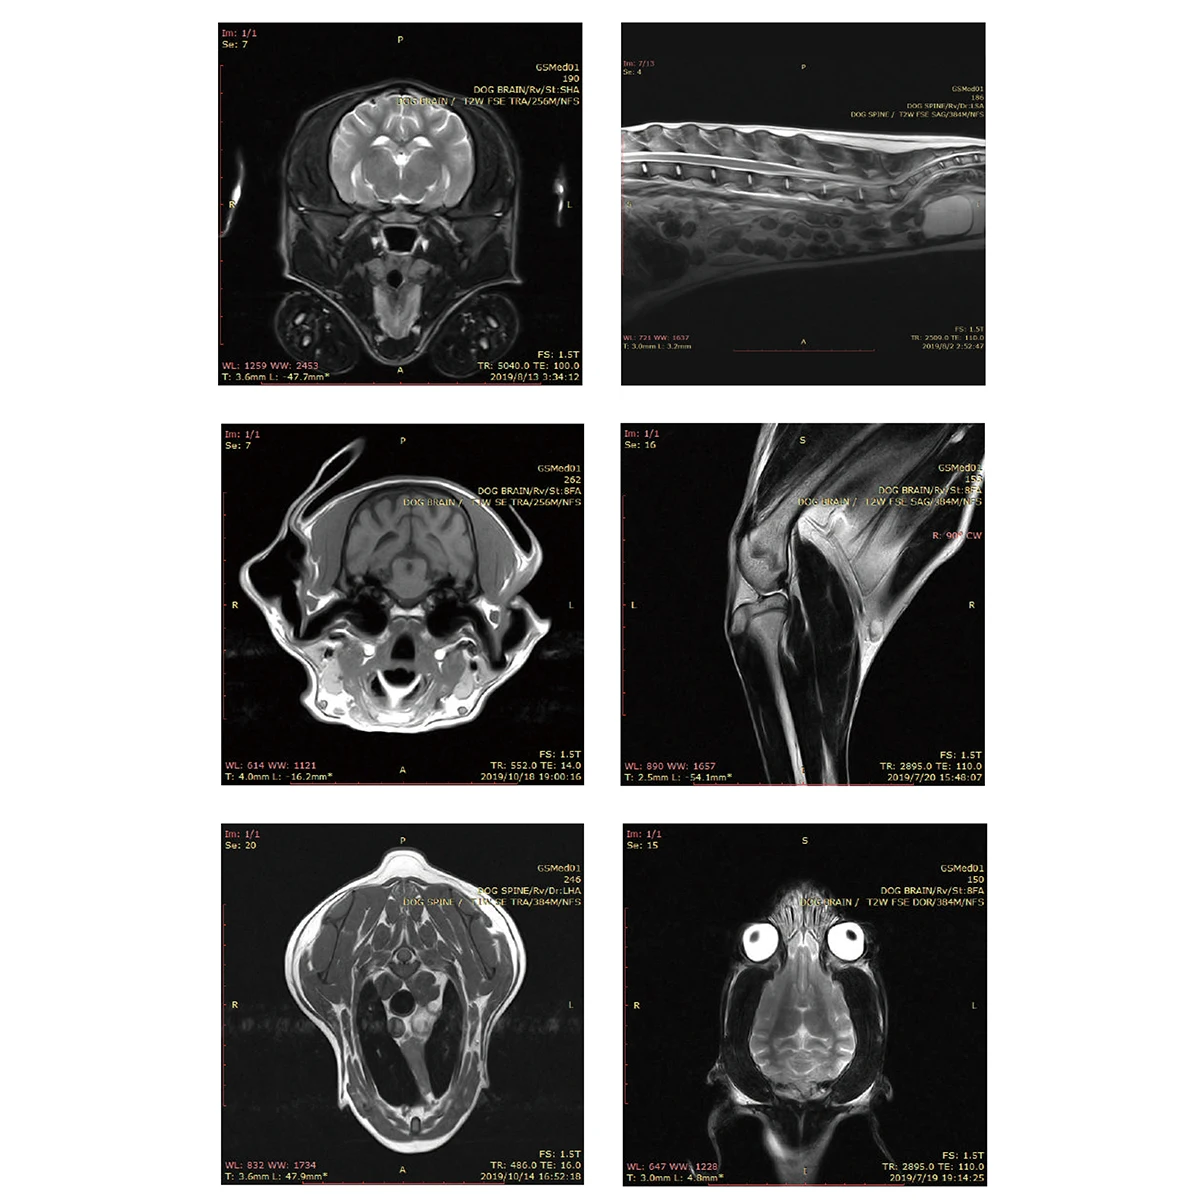

Мрт ветеринария 140 фото